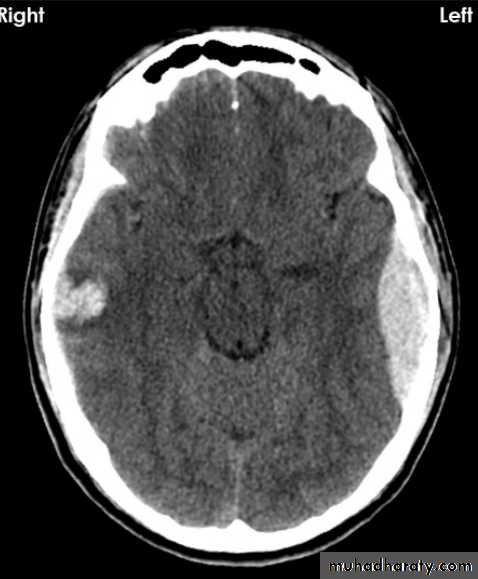

Acute EDH

CT finding

Hyper density area, 50-70 HU, due to the clotted blood, elliptical in shape, no edema around the lesion, but may cause shifting of the midline, or compression of the ipsi lateral ventricle if it is large enough.

The source of bleeding of the haematome is injured middle meningeal artery so the lesion > 90 % associated with skull # at the site of the previous mentioned artery.

EDH

Biconvex hyper density area

Shifting of the midline

Compression of the ventricles